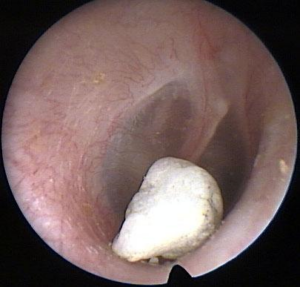

Look at these pictures of the inside of the ear. Do they look healthy?

No. There is a foreign body in the ear canal.